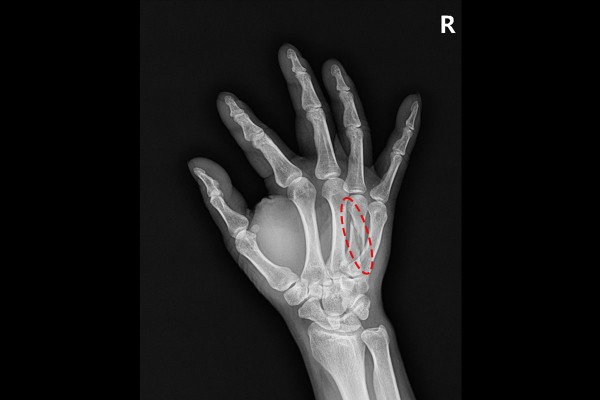

양주 옥정에 거주하시는 43세 남성 환자분께서 우측 손 중수골 골절로 내원해주셨습니다. 환자분께서는 내원 5일 전에 업무중 다치셔서 근처 타병원을 들려 X-RAY와 CT 검사 진행 후 수술이 필요하다는 소견을 듣고서 소개로 저희 병원을 내원해주셨습니다.

환자분께서 지참해오신 X-RAY를 보면 4번째 중수골에 나선형 골절이 확인됩니다.